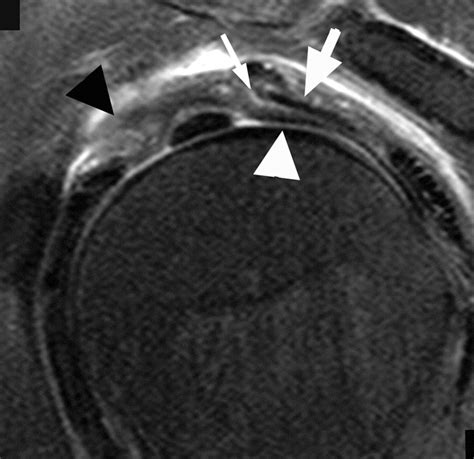

The rotator cuff interval is a triangular space located in the anterior-superior aspect of the shoulder joint. It is bordered by the superior margin of the subscapularis tendon and the anterior margin of the supraspinatus tendon. The base of this triangle is formed by the coracoid process, while the apex extends toward the intertubercular groove of the humerus. Several vital structures traverse this interval, playing a pivotal role in shoulder stability:

• Coracohumeral Ligament (CHL): A primary stabilizer that prevents inferior translation of the humeral head.

• Superior Glenohumeral Ligament (SGHL): Provides resistance to external rotation and helps secure the humeral head.

• Long Head of the Biceps Tendon (LHBT): Travels through the interval before entering the joint space, acting as a dynamic stabilizer.

Magnetic Resonance Imaging (MRI) The gold standard for visualizing soft tissue, ligamentous thickening, and interval tears.

Magnetic Resonance Arthrography (MRA) Provides enhanced detail by injecting contrast into the joint, ideal for detecting minor labral or interval ligament tears.